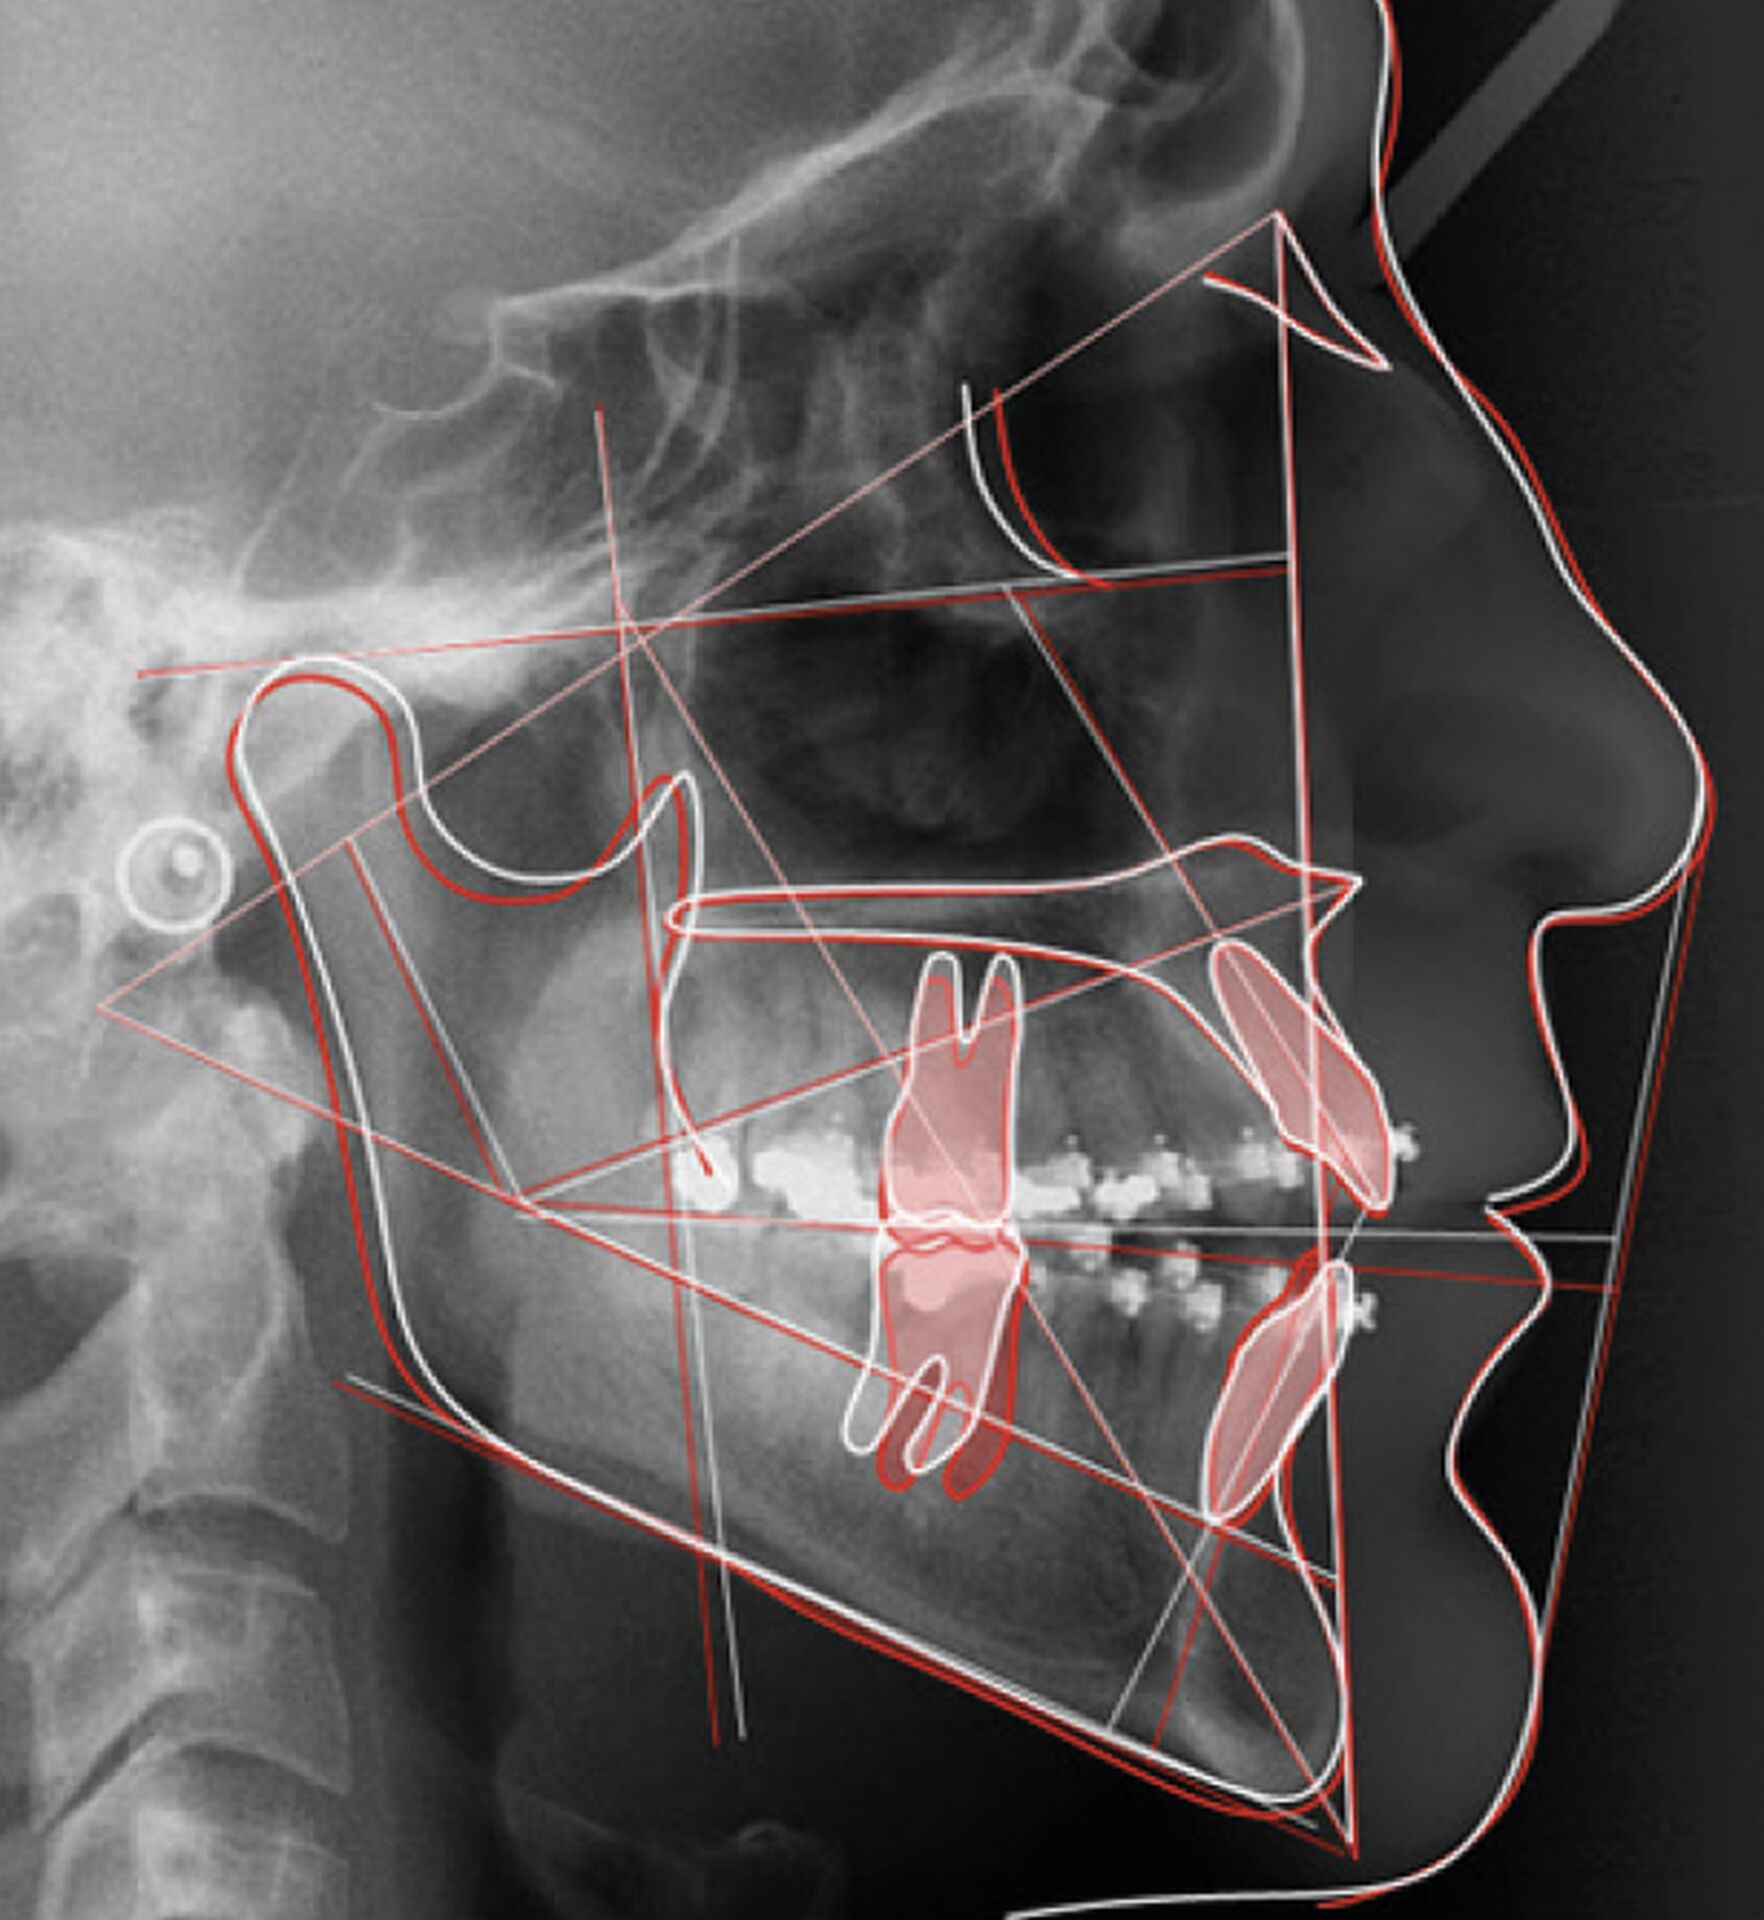

Ceph Analysis est un logiciel d’orthodontie puissant et révolutionnaire, développé par Owandy Radiology, conçu pour automatiser et simplifier le tracé céphalométrique grâce à l’Intelligence Artificielle. Cette technologie identifie automatiquement les points de repère, plans et silhouettes des tissus durs et mous sur les radiographies latérales ou postéro-antérieures en quelques secondes, permettant ainsi un gain de temps considérable et une précision constante.

Le logiciel offre une analyse et superposition d’images automatique ou manuelle, permettant de comparer l’évolution du patient et de générer des rapports détaillés. La fonction de projection de croissance simule l’évolution crânienne de l’âge squelettique actuel à un âge futur, offrant une vision prospective du développement du patient jusqu’à la maturité.

• Plus de 200 types d’analyses céphalométriques intégrées et personnalisables